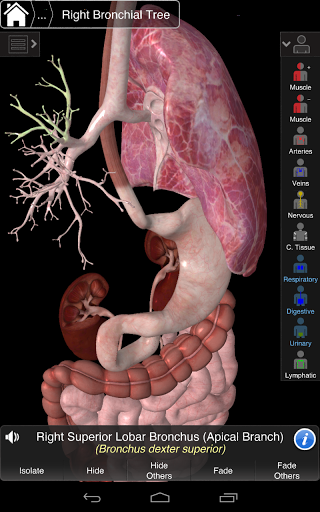

Essential Anatomy 3 représente la toute dernière technologie 3D révolutionnaire et un design innovant. Un moteur graphique 3D de pointe, construit sur mesure par 3D4Medical à partir de zéro, alimente un modèle anatomique très détaillé et fournit des graphiques de qualité exceptionnelle qu'aucun autre concurrent ne peut atteindre.

L'application représente une approche unique à l'apprentissage de l'anatomie générale. Les graphismes sont inégalés et rendent l'apprentissage, grâce à l'utilisation de contenu informatif et de fonctionnalités innovantes, une expérience riche et engageante.

NOUVELLE TECHNOLOGIE 3D

Essential Anatomy 3 est réactif, visuellement magnifique et sans effort. L'application est entièrement 3D, ce qui signifie que vous pouvez voir n'importe quelle structure anatomique dans l'isolement, ainsi que de n'importe quel angle.

---- Plus de 4000 structures anatomiques très détaillées

---- Nomenclature latine pour chaque structure anatomique